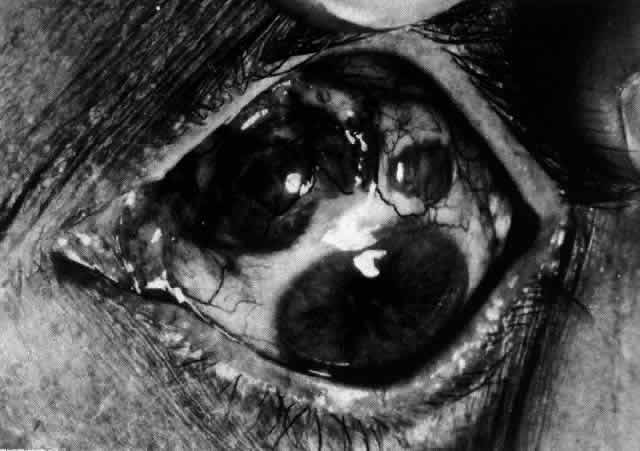

The onset of scleritis is usually gradual, building up over several days. By the time patients seek advice, the clinical types can be distinguished as anterior or posterior, or occasionally both. Anterior scleritis may be further subdivided into diffuse, nodular, or necrotizing. The last condition may present with signs of inflammation or with few or no signs of inflammation (scleromalacia perforans). Long-term follow-up of patients with scleral disease showed that only 8% of patients changed from one type of disease to another during the course of this disease, so although differentiation into these types does not usually indicate an etiology, it does have a direct bearing on the prognosis and the type of treatment to be used.10

Scleritis is most common in the fourth to sixth decades of life and occurs more frequently in women than men (8:5). Necrotizing scleritis occurs later than the other varieties, the mean age being 61 years. Scleritis is bilateral in 52% of patients. In half of these, the condition starts in both eyes simultaneously, with the rest becoming bilateral in 5 or more years.

Necrotizing Anterior ScleritisdWithout Adjacent Inflammationd(Scleromalacia Perforans)

Necrotizing anterior scleritis without adjacent inflammation appears to be a well-defined condition with little relation in clinical features to necrotizing scleral disease, even though the pathology is similar and the final result is the same. Scleromalacia perforans is characterized by the almost total lack of any symptoms. It occurs almost exclusively in patients with long-standing polyarticular rheumatoid arthritis, the majority of whom are female (Figs. 49 and 50; Color Plate 1E).

Fig. 49. A white necrotic plaque developing in an area of sclera with practically no surrounding inflammation in a 60-year-old woman who had had Crohn's disease for 17 years.

Fig. 50. Scleromalacia perforans after treatment. The very thin sclera is covered by conjunctiva only and a few remaining large blood vessels. (Courtesy of Mr. HE Hobbs)

The anterior sclera loses its covering of episclera and develops an area of yellow-white necrotic slough over many months; this eventually separates or is absorbed, leaving the underlying choroid covered by either conjunctiva or nothing at all. As with necrotizing disease, the choroid does not bulge into this ectatic area; but unlike necrotizing disease, spontaneous healing of even small perforations is very limited once the necrotic tissue has been removed (see Fig. 50).

Fluorescein angiography is not helpful, except to indicate areas of vascular closure in an otherwise extremely thin, atrophic episcleral tissue.4 The formation of a sequestrum appears to be caused by arteriolar closure as opposed to the venular disease seen in the other forms of necrotizing scleritis.